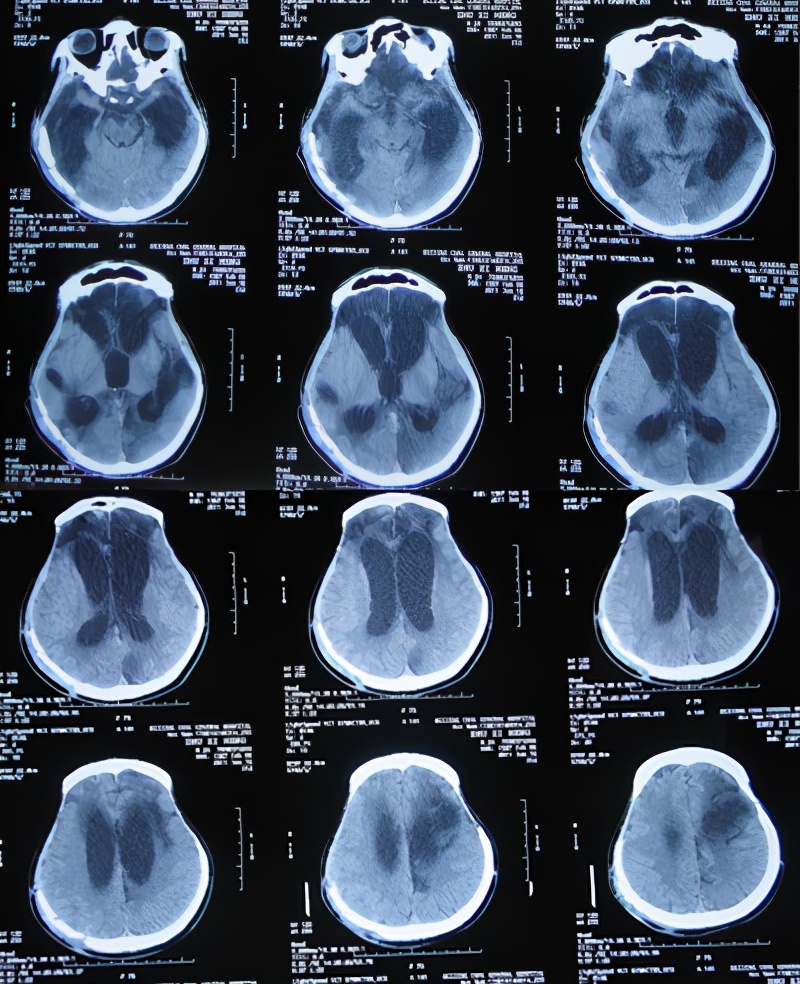

在第2家医院治疗45天时即2011年4月6日即开颅术后81天,仍能简单的遵嘱活动,能简单言语,如“爸爸、妈妈”;查头颅CT示:颅骨缺损,仍脑水肿,且出现脑室扩张( 图-4 );但没有给予处理。

图-4: 2011年4月6日头颅CT

随后立即给予腰大池引流和抗感染治疗,27天后即2011年5月27日(干细胞移植治疗31天后即开颅术后132天),患者病情反而更加重,意识变差,仍间断发热;查头颅CT示仍脑积水和水肿变得更加严重( 图-5 ),因此不得不转入该院的重症监护室。

图-5: 2011年5月27日头颅CT

重症监护室治疗20天即2011年6月16日(干细胞移植治疗51天后即开颅术后152天),患者意识稍有好转,体温也变为正常;查头颅CT示脑积水仍未见改善( 图-6 ),所以转回普通病房。

图-6: 2011年6月16日头颅CT